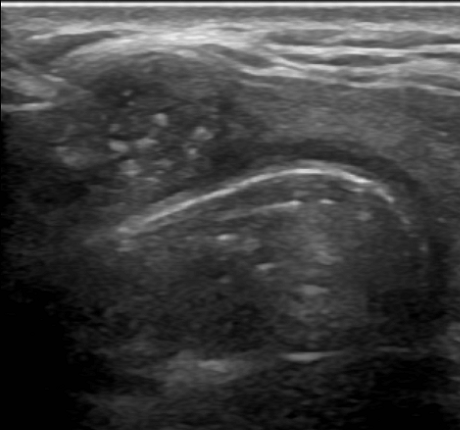

여포성 종양(follicular neopl asm, 소포신생물)이 의심되어 세침흡인검사를 실시하고

다행히도 베세다 시스템II에서 양성결절로 추적을 할 예정입니다

여포성 종양(follicular neoplasm)이라는 선종(aemoma)은 갑상선 결절의 5~10% 정도를 차지하며 여포성 종양(follicular neoplasm. 혹은 소포신생물)과 허들세포 선종(Hurthle celladenoma) 등이 있습니다. 세포소견만으로는 여포성 종양과 여포성 암(foillcular cancer)을 구별할 수 없으므로 세침흡인 검사에서 여포성 종양(follicular neoplasm)이 진단된 경우 수술을 통해 확인해야 합니다.